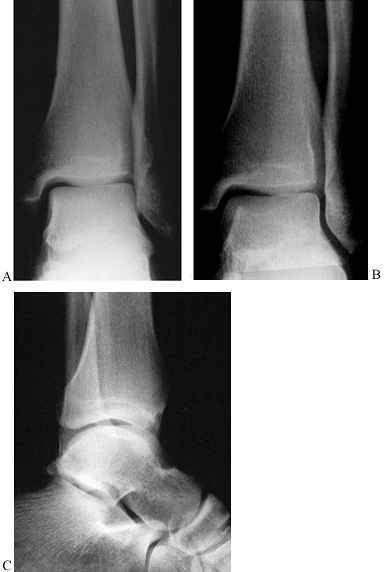

anteroposterior, lateral, and mortise views. The anteroposterior view

sagittal plane (Fig. 25.4A). The lateral view is taken with the beam centered on the ankle joint and directed in the frontal plane (Fig. 25.4B).

The mortise view is taken with the leg internally rotated about 15° so

the x-ray beam passes perpendicular to the axis of movement (Fig. 25.4C).

The anteroposterior view combined with the mortise view allows

detection of avulsion fractures of the malleoli, vertical fractures of

the medial malleolus, and lateral subluxation of the talus. The lateral

view is most helpful in outlining the configuration of the lateral

malleolar fracture and in detecting anterior and posterior tibial

fractures.

Figure 25.4. A: A true anteroposterior view along the axis of the foot. B:

The true mortise view with the foot internally rotated 15° clearly shows the entire joint space extending from the tip of the medial malleolus to the tip of the lateral malleolus. C:The lateral view of the ankle joint, showing the fibula line posterior to the tibia. |